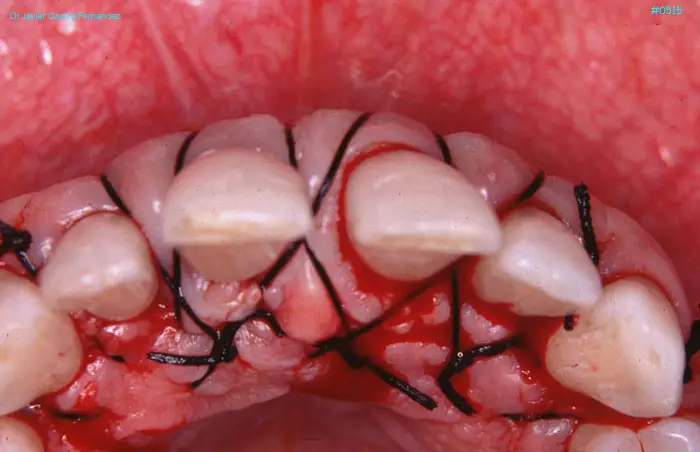

Atlas of Surgical Techniques in Periodontics. Chapter II. Atlas de Técnicas Quirúrgicas en Periodoncia